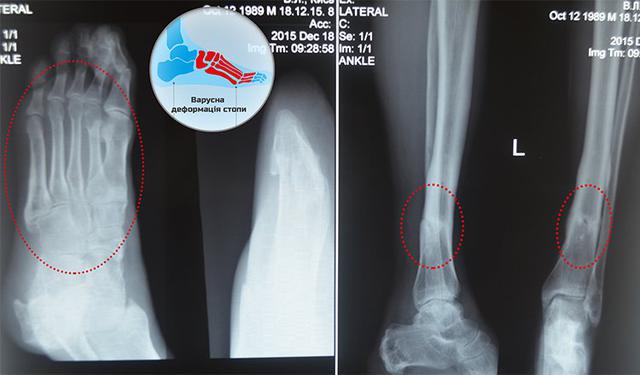

"Виталий получил ранения еще летом 2014-го. Во время боя у Саур-Могилы танк Виталия попал под мощный минометный обстрел. Взрывы сбросили тяжелую боевую машину с моста, боец получил серьезные травмы - повредило ногу и живот. Последующие пять операций в государственных госпиталях облегчения не принесли: хотя раны живота и вылечили, тяжело поврежден нога срослась неправильно. Стопу сильно выкрутило, к тому же, из-за искалеченные кости, нога серьезно укоротилась. Конечно, ходить самостоятельно Виталий не мог - этому помешали постоянные сильные боли и отеки в деформированной ноге", - рассказали в "Народном проекте".

В проект "Биотех-реабилитация раненых" Виталий обратился в январе 2016 года. Со временем костям Виталия предоставили правильную форму с помощью аппарата Илизарова, а места костных дефектов наполнили медицинским гелем, насыщенным собственной клеточной тканью пациента.

"Со временем кости ноги приобрели правильную форму, все травматические зоны заросли собственной костной тканью, и нога вернулась к естественной форме. Месяц назад аппарат Илизарова сняли, а сейчас очередь дошла и до гипса: ногу Виталия в полной мере освободили из "плена". Дальше дело только за реабилитацией: ногу надо снова приучать к нагрузкам, и теперь Виталий получил возможность ходить уже самостоятельно. Мы уверены, что его усилия приведут к наилучшему результату".